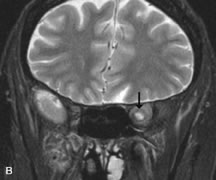

Lymphomas have MRI characteristics similar to those of inflammatory lesions in that they are hypointense to fat and isointense to muscle on T1-weighted images (Fig. 22). They may appear hyperintense to fat on T2-weighted images, perhaps owing to less fibrosis than that seen in orbital inflammatory pseudotumor, although this is not a consistent finding.31,50,66 Lymphoid tumors typically enhance moderately after contrast injection. Unfortunately, studies have shown that tumor density and homogeneity are similar between inflammatory and malignant orbital infiltrates, and MRI cannot differentiate these lesions.72,73

Fig. 22. A and B. T1- and (C) T2-weighted MR scans demonstrate a poorly defined multicompartmental mass enveloping the lateral rectus, superior rectus, and levator palpebrac superioris muscles. The lesion is isointense to brain on T1- and T2-weighted scans, as is typical for highly cellular neoplasms. D. Postcontrast fat-suppressed T1-weighted scan demonstrates intense enhancement of the infiltrating intraconal and extraconal tumor.